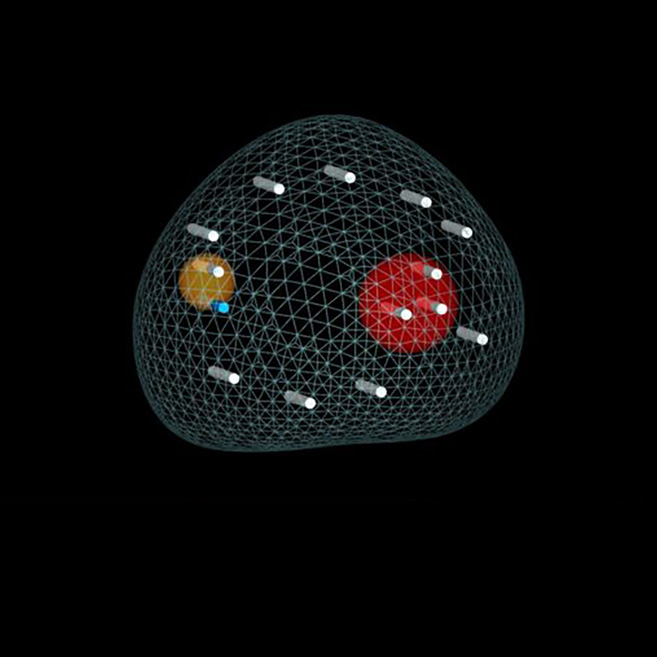

The Only 3D Ultrasound Platform That Automatically Compensates for Prostate and Patient Movement

Unlike other systems which disrupt surgical workflow and require the surgeon to manually realign MRI and ultrasound images during the procedure – KOELIS® Trinity’s intuitive Organ Based Tracking Fusion® software automatically performs image realignment, resulting in exceptional biopsy targeting accuracy.

Our integrated 3D ultrasound system generates high-res 3D prostate renderings—enabling real-time fusion with other technologies such as MRI.

With PROMAP-FT, you can better plan, guide and monitor needle-based focal therapy techniques within the Trinity® system.